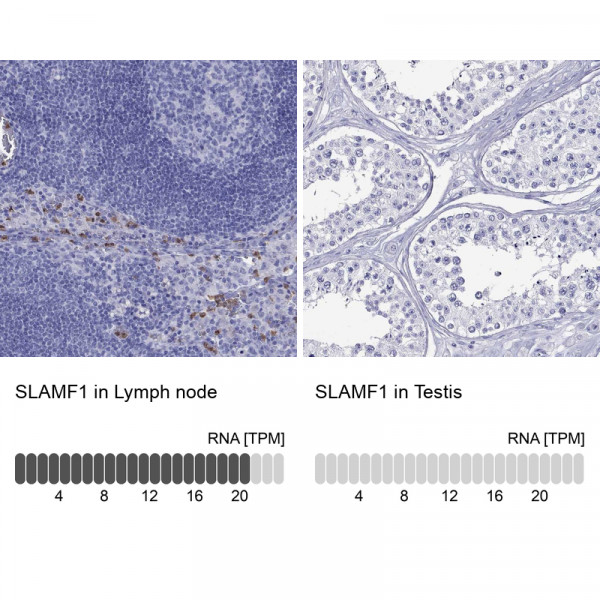

Product information "Anti-SLAMF1"

Protein function: Self-ligand receptor of the signaling lymphocytic activation molecule (SLAM) family. SLAM receptors triggered by homo- or heterotypic cell-cell interactions are modulating the activation and differentiation of a wide variety of immune cells and thus are involved in the regulation and interconnection of both innate and adaptive immune response. Activities are controlled by presence or absence of small cytoplasmic adapter proteins, SH2D1A/SAP and/or SH2D1B/EAT-2. SLAMF1-induced signal-transduction events in T-lymphocytes are different from those in B-cells. Two modes of SLAMF1 signaling seem to exist: one depending on SH2D1A (and perhaps SH2D1B) and another in which protein-tyrosine phosphatase 2C (PTPN11)-dependent signal transduction operates. Initially it has been proposed that association with SH2D1A prevents binding to inhibitory effectors including INPP5D/SHIP1 and PTPN11/SHP-2 (PubMed:11806999). However, signaling is also regulated by SH2D1A which can simultaneously interact with and recruit FYN which subsequently phosphorylates and activates SLAMF1 (PubMed:12458214). Mediates IL-2-independent proliferation of activated T-cells during immune responses and induces IFN-gamma production. Downstreaming signaling involves INPP5D, DOK1 and DOK2 leading to inhibited IFN-gamma production in T-cells, and PRKCQ, BCL10 and NFKB1 leading to increased T-cell activation and Th2 cytokine production. Promotes T-cell receptor-induced IL-4 secretion by CD4(+) cells. Inhibits antigen receptor- mediated production of IFN-gamma, but not IL-2, in CD4(-)/CD8(-) T- cells. Required for IL-4 production by germinal centers T follicular helper (T(Fh))cells. May inhibit CD40- induced signal transduction in monocyte-derived dendritic cells (PubMed:16317102). May play a role in allergic responses and may regulate allergen-induced Th2 cytokine and Th1 cytokine secretion. In conjunction with SLAMF6 controls the transition between positive selection and the subsequent expansion and differentiation of the thymocytic natural killer T (NKT) cell lineage. Involved in the peripheral differentiation of indifferent natural killer T (iNKT) cells toward a regulatory NKT2 type. In macrophages involved in down-regulation of IL-12, TNF-alpha and nitric oxide in response to lipopolysaccharide (LPS). In B-cells activates the ERK signaling pathway independently of SH2D1A but implicating both, SYK and INPP5D, and activates Akt signaling dependent on SYK and SH2D1A. In B-cells also activates p38 MAPK and JNK1 and JNK2 (PubMed:20231852). In conjunction with CD84/SLAMF5 and SLAMF6 may be a negative regulator of the humoral immune response. Involved in innate immune response against Gram-negative bacteria in macrophages, probably recognizes OmpC and/or OmpF on the bacterial surface, regulates phagosome maturation and recruitment of the PI3K complex II (PI3KC3-C2) leading to accumulation of PdtIns(3)P and NOX2 activity in the phagosomes (PubMed:20818396). [The UniProt Consortium] Buffer: 40% glycerol and PBS (pH 7.2). 0.02% sodium azide is added as preservative. Highest antigen sequence identity to mouse: 48% and to rat: 49%

| Application: | IHC |